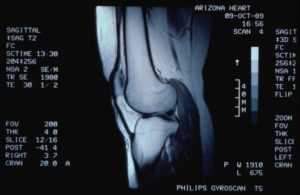

В диагностике тромбоза вен подколенной области используются функциональные пробы и ультразвуковое исследование. Функциональные пробы – это пробы Рамирезева, Мозера, Хоманса, Ловенберга. Одним из наиболее часто используемых тестов является тест Ловенберга, при котором манжета накладывается на голень ниже места предполагаемого тромба.

Давление нагнетается до 100 мм рт. В этом случае человек начинает испытывать болезненные ощущения на месте тромбоза. Как правило, на здоровой конечности боль может возникнуть при повышении давления до 160 мм рт. Также можно использовать пробы давления, при которых боль возникает при надавливании на различные части голени при сгибании. Такой положительный тест свидетельствует о наличии тромбоза.

Одним из основных и наиболее точных методов диагностики тромбоза является цветоконтрастное ультразвуковое исследование, а также ультразвуковая допплерография. Такие методы позволяют узнать точную локализацию тромба.